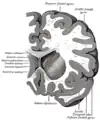

The caudate nuclei are located near the center of the brain, sitting astride the thalamus. There is a caudate nucleus within each hemisphere of the brain. Individually, they resemble a C-shape structure with a wider "head" (caput in Latin) at the front, tapering to a "body" (corpus) and a "tail" (cauda). Sometimes a part of the caudate nucleus is referred to as the "knee" (genu).[7] The caudate head receives its blood supply from the lenticulostriate artery while the tail of the caudate receives its blood supply from the anterior choroidal artery.[8]

The head and body of the caudate nucleus form part of the floor of the anterior horn of the lateral ventricle. After the body travels briefly towards the back of the head, the tail curves back toward the anterior, forming the roof of the inferior horn of the lateral ventricle. This means that a coronal (on a plane parallel to the face) section that cuts through the tail will also cross the body and head of the caudate nucleus.